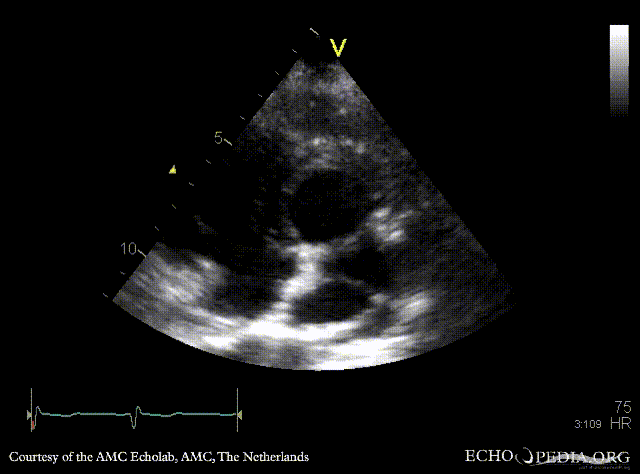

Abnormal pulmonary vein drainage

PSAX with Color Doppler A3CH with Color Doppler